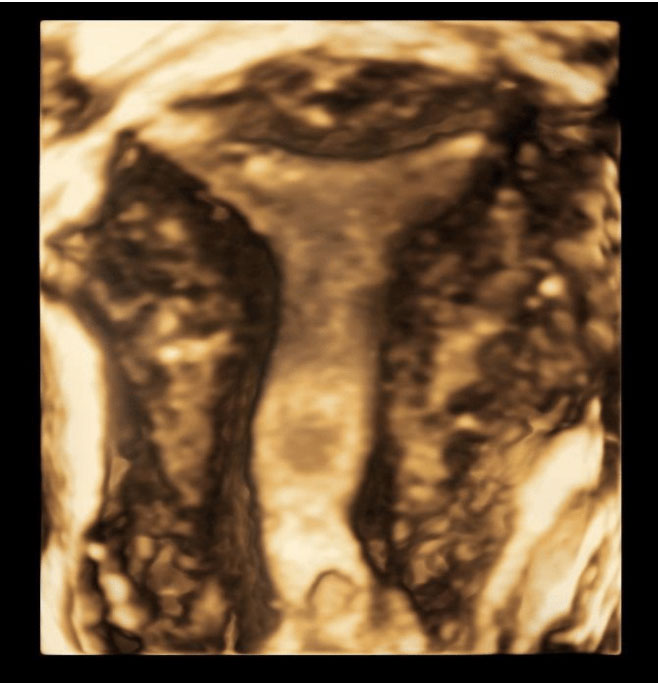

Cervical Length Scan

Women who have experienced a previous second trimester miscarriage or a previous early preterm birth (before 32 weeks) may benefit from cervical surveillance. Cervical surveillance involves performing a transvaginal ultrasound to assess the length of the cervix. This is usually done every 2 weeks from 14 weeks to 28 weeks. If the cervix appears short, the specialist will discuss the options for treatment with your referring doctor. In some cases, this might involve Progesterone pessaries or insertion of a stitch into the cervix to keep it closed.